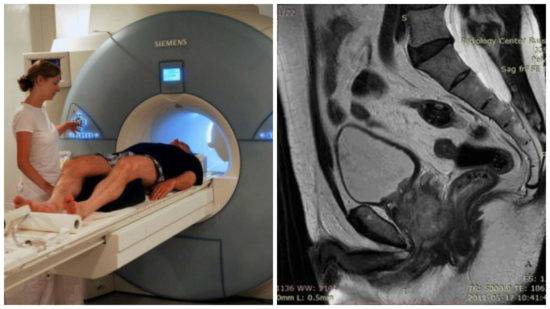

Компьютерная томография органов малого таза: оборудование и результаты исследований

Раздел: Галерея прозрений